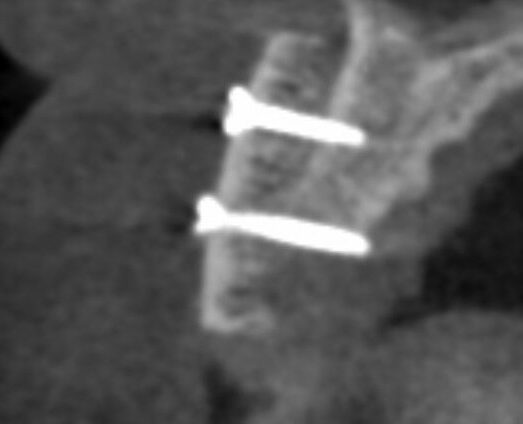

Greffe osseuse: Dans certains cas, la quantité d’os disponible dans la mâchoire n’est pas suffisante pour poser un implant de manière stable et durable. Pour recréer un volume adapté, différentes chirurgies pré-implantaires peuvent être proposées :

La greffe d’apposition (horizontale ou verticale) : cette technique consiste à ajouter de l’os pour élargir ou rehausser la mâchoire. Elle permet d’obtenir une base osseuse solide et adaptée à la pose de l’implant.

Le sinus lift (accès par voie latérale) : lorsqu’il manque de l’os en arrière du maxillaire supérieur, on accède au sinus par une paroi latérale et on le comble avec nos matériaux. Cela augmente la hauteur osseuse disponible.